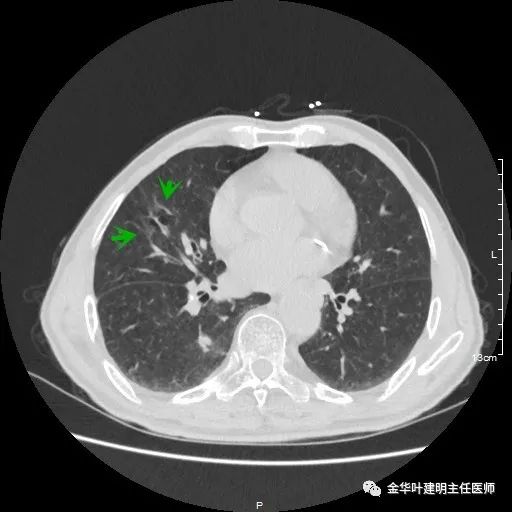

金华的某A,今年已经80岁了,前些天检查发现右下肺部占位,让我会诊。我打开电脑一看图,发现右下肺是典型的实性分叶状的占位,基本可肯定肺癌,余肺仍有多处磨玻璃影及类似慢性炎的病灶,是不是合并炎症?还是多原发肺癌?鉴于其中叶肺门部混合磨玻璃结节边缘略显模糊,为了防止炎性病灶,让其进行了10天的静脉抗炎治疗,但复查靶扫描后发现病灶无任何吸收好转,靶扫描上把细节显示的更清楚了,反而更坚定了我判断其为肺癌的结论。对于这样年纪的多原发癌,我们该如何来进行临床思考呢?治疗该如何建议与决策?当然最后的结果要如实告知患方后,由他们自己决定。

以上示右下叶病灶5。也是主病灶,是实性块状分叶的占位性病变,基本可以肯定是肺癌。单病灶看需下叶切除并清扫淋巴结。

以上示右下叶病灶6。同样是囊腔型病灶,但较前几个范围小,可囊壁同样为磨玻璃影,也是较为典型的囊腔型肺癌表现,单灶来看可下叶背段切除。